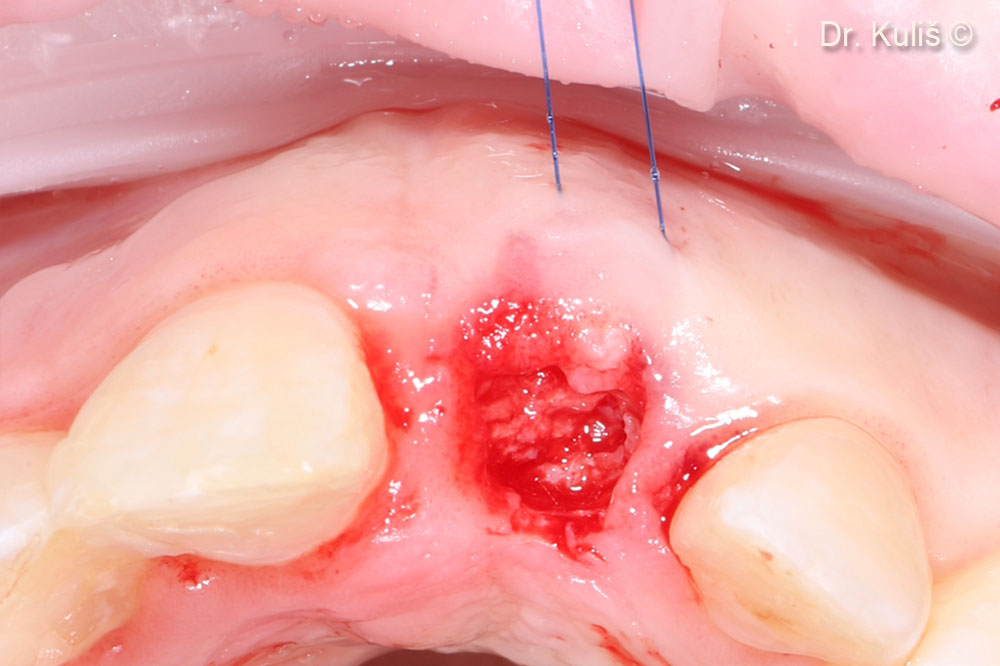

Vị trí cấy ghép có đường kính 3,75mm.

Tăng cường xương bằng mp3®

Màng tế bào Evolution đã được điều chỉnh để phù hợp với khiếm khuyết.